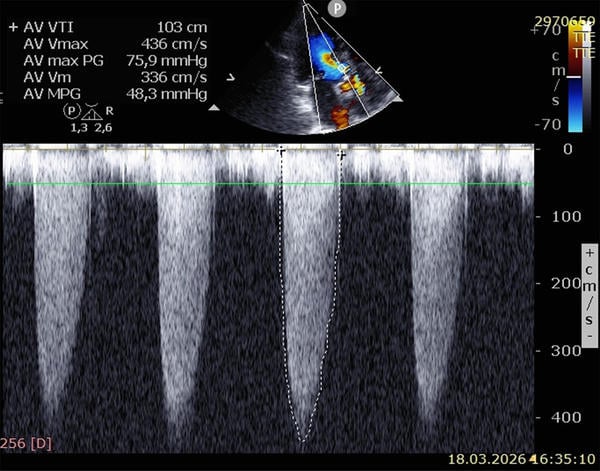

Echocardiography

- Normal systolic left and right ventricular function (EF ~ 65%)

- Moderate concentric hypertrophy

- High-flow aortic valve stenosis (maximum gradient 76 mmHg, mean gradient 48 mmHg, no aortic valve insufficiency)

- Grade I mitral and tricuspid valve insufficiency

- Estimated pulmonary artery pressure ~ 25 mmHg